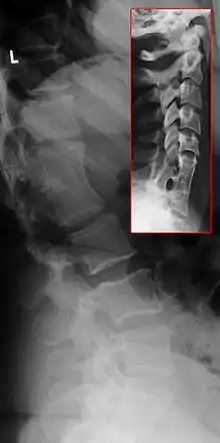

Syndrome de Klippel-Feil

Le syndrome de Klippel-Feil ou SKF (en anglais, Klippel-Feil syndrome ou KFS) est caractérisé par un défaut de segmentation des somites cervicaux, résultant en une fusion congénitale de vertèbres cervicales.

Aujourd'hui, n'importe quelle fusion congénitale d'au moins deux vertèbres est considérée comme une manifestation du syndrome de Klippel-Feil.

Une classification est proposée indépendamment dès 1919 par André Feil et Maurice Klippel. Ils ont décrit des patients avec un pterygium colli, une réduction de la gamme de mouvement dans la colonne cérébrale et une base des cheveux anormalement basse. Feil par la suite a proposé une classification du syndrome dans trois catégories:

- Type 1 - Fusion de C2 et C3 avec occipitilisation de l'atlas. McRae en 1953 a complété la définition du Type 1.

- Type 2 - Longue fusion en dessous de C2 avec une jonction anormale occipito-cervical. Le problème dans ce cas peut se situer au niveau thoracique. Il s'agit de la forme la plus répandue du syndrome[4].

- Type 3 - Une ouverture de l'espace situé entre deux sections vertébrale fusionnée. Le type 3 peut être aisément distingué des type 1 et 2, par la présence d'une inflexion au niveau du segment ouvert.